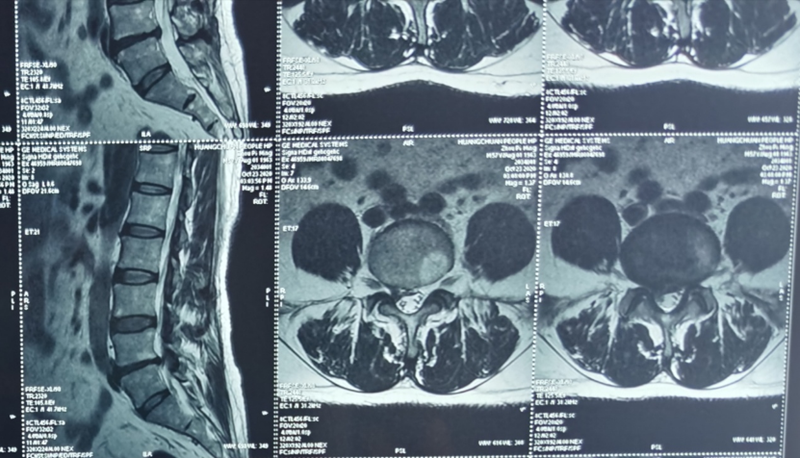

经过苏医师仔细全面的检查,确诊为腰椎间盘突出,建议周先生进行椎间孔镜微创手术,并详细的介绍了椎间孔镜手术创口小、恢复快,不影响工作和生活的优点,还有市级专家到院亲自指导手术,周先生这才打消顾虑接受手术。

2020年10月31日,在省级专家的指导下,周先生的手术顺利完成,术后恢复良好,隔日下地活动自如。周先生高兴地说:真是太神奇了!我以前了解的传统手术不仅要切开10至15厘米左右的切口,还需3个月左右才能康复,这次的手术两小时就做完了,微创切口只有一厘米,就缝了一针,没受一点罪,这才一个星期就能出院了。